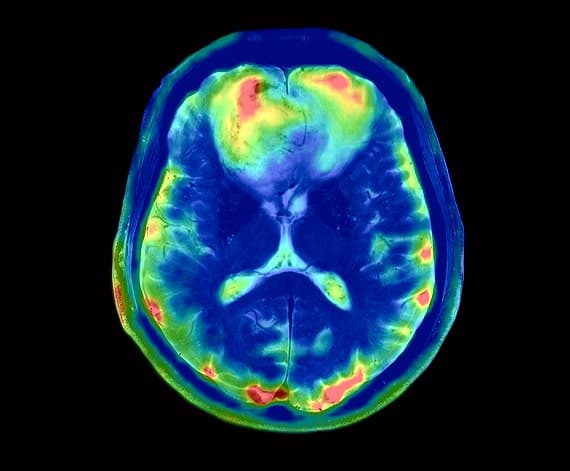

DTI (Diffusion Tensor Imaging)

Visualizing White Matter Integrity. Our DTI technology maps microscopic water movement in the brain to identify axonal shearing and subtle Traumatic Brain Injuries (TBI) that standard MRIs often miss.